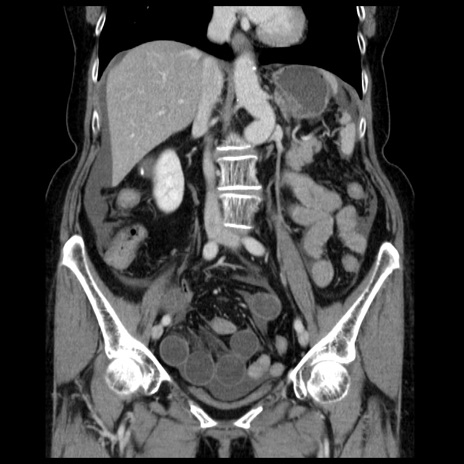

症例13(冠状断像)

【症例】70歳代女性

【主訴】腹痛、嘔吐

【現病歴】15時間程前(昨晩)より腹痛あり。今朝になっても症状の改善なく、嘔吐あり。腹痛も増悪あり、救急外来受診。

【既往歴】子宮癌全摘術後

【身体所見】意識清明、BP 121/72mmHg、P 74bpm、SpO2 100%(RA)、腹部:平坦・軟、腸雑音ほぼ聴取せず。下腹部・心窩部・臍左上に圧痛あり。反跳痛なし。

【データ】WBC 10600、CRP 0.15